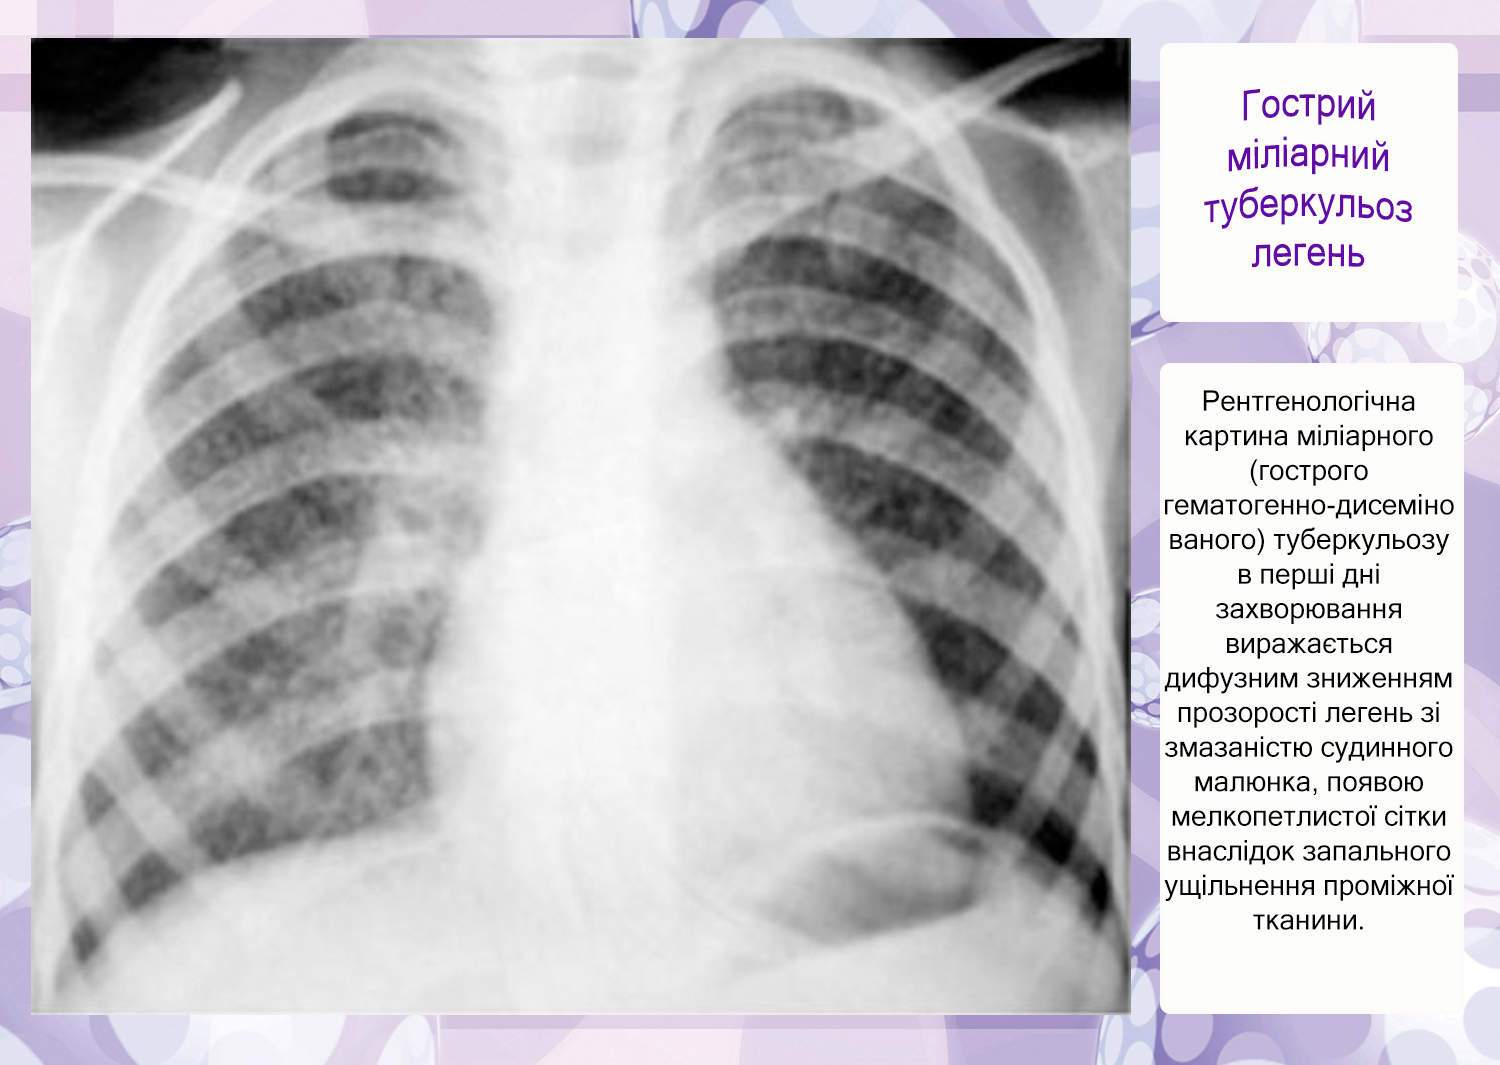

Милиарный туберкулез у детей: симптомы и лечение